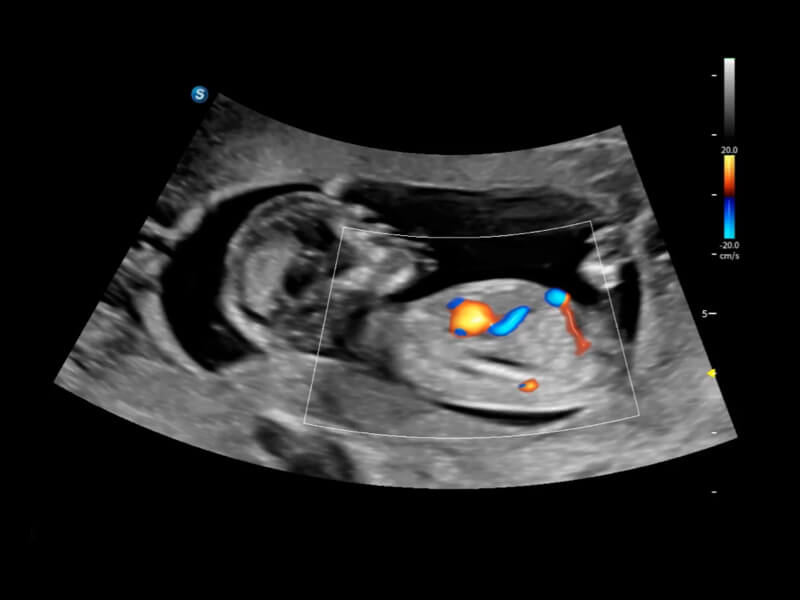

豐富的血流動(dòng)力學(xué)檢測(cè)技術(shù),可在不同醫(yī)療場(chǎng)景中高效捕捉血流信號(hào),助力臨床診療。

在傳統(tǒng)血流的基礎(chǔ)上優(yōu)化掃查和算法策略,能夠更好的抑制組織信息,提煉紅細(xì)胞運(yùn)動(dòng)信息,得到更高幀頻,高靈敏度和分辨率的血流信號(hào),還原更真實(shí)的血流動(dòng)力學(xué)。

通過光照模型,使二維血流顯示出立體的效果,增加血流的敏感性、成束性,減少外溢??梢院推渌煌难骷夹g(shù)聯(lián)合使用,融合不同技術(shù)的優(yōu)勢(shì)。輕松應(yīng)對(duì)微小血管,增強(qiáng)血流的立體效果,提升視覺敏感性。

通過創(chuàng)新的Matrix E自適應(yīng)濾波算法,能有效濾除軟組織和噪聲信號(hào),最大限度保留超低速微細(xì)血流的信號(hào);結(jié)合超長時(shí)間域算法,極大提升細(xì)微血流的敏感性和空間分辨率,更真實(shí)的反應(yīng)組織、包塊的血流灌注情況。